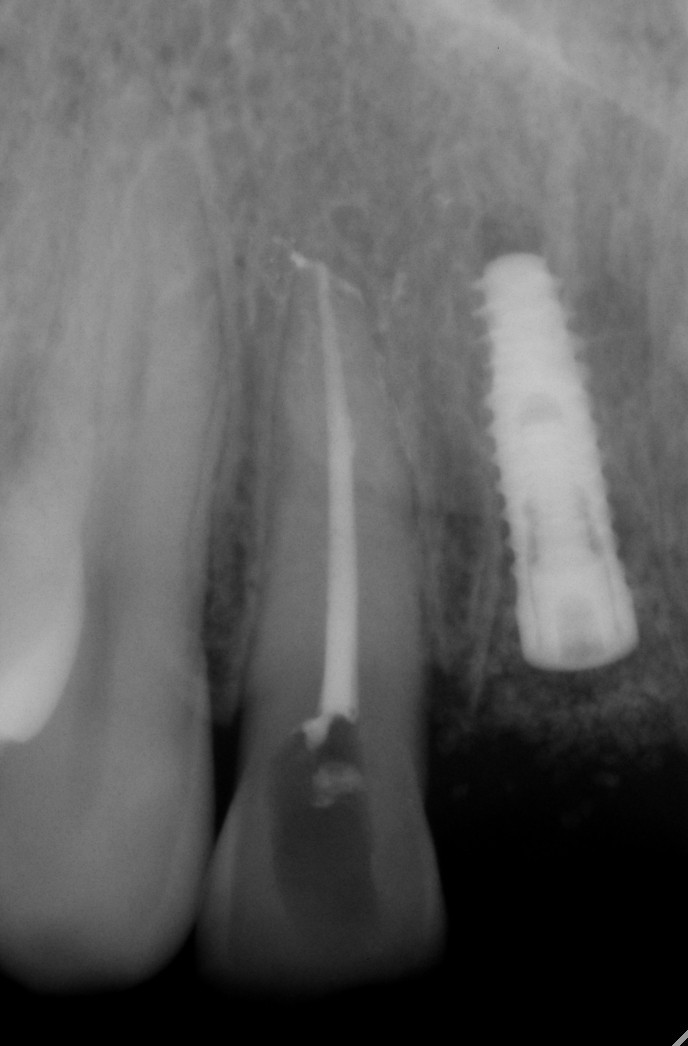

数字化根尖片

诊断范围涉及牙体牙髓病、牙周病、阻生牙/多生牙定位、种植牙术前CT评估分析、颞下颌关节CT诊断分析、,颌骨及涎腺疾病、颌面发育畸形、正畸治疗辅助诊断等大部分颌面部疾病,为临床医疗提供强有力的支持。